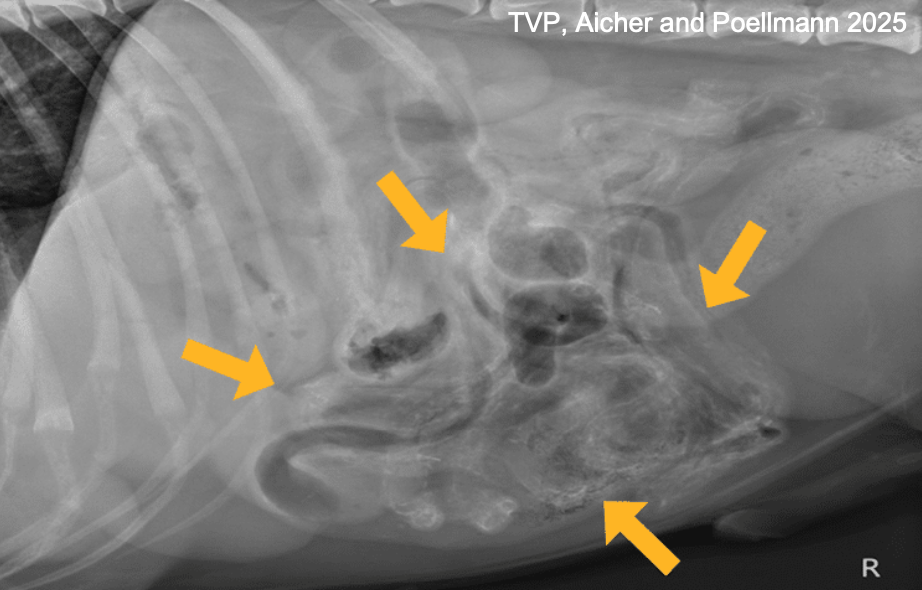

what will be seen on imaging in dogs infected with heterobilharzia americana?

rads: multifocal areas of mineralization within organs (calcified eggs)

ultrasound: pinpoint hyperechoic foci in visceral organs